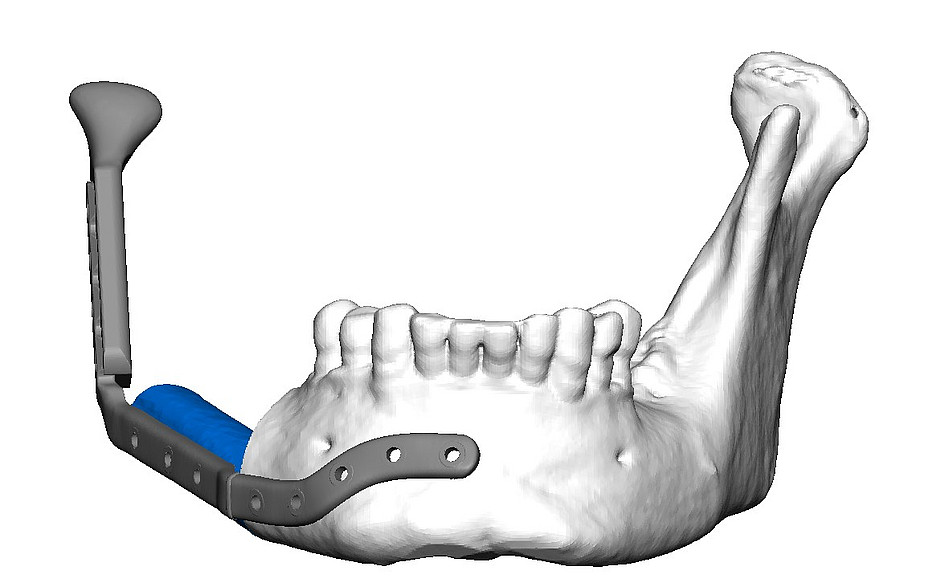

Die ablative und traumatische Gesichtschirurgie kann mit dramatischen Veränderungen der Gesichtsgeometrie assoziiert sein, so dass ein sekundärer Korrektureingriff zur Wiederherstellung der Funktion und Ästhetik notwendig sein kann. Mit konventionellen Behandlungsmöglichkeiten ist oftmals keine originalgetreue Rekonstruktion betroffener Strukturen möglich, weshalb unsere Forschungsgruppe daran arbeitet, den Einsatz der computer-assistierten Chirurgie in diesem Feld voranzutreiben. Dazu werden sogenannte Patientenspezifische Implantate so designt, dass zuerst das ästhetisch wünschenswerte Endergebnis simuliert wird, indem das Ausmaß des Weichteilgewebes dargestellt wird und von diesem Ziel ausgehend rückwarts geplant wird, wie die knöchernen Strukturen rekonstruiert werden müssen. Diese Art der Planung unterscheidet sich deutlich von anderen Planungen und ist auch weitaus komplexer. Trotz hochauflösender CT und MRT-Aufnahmen kann nicht auf jede kleine Weichgewebsstruktur und deren elastisches Verhalten eingegangen werden, aber durch die Planung kann dieses Problem durch eine gewisse Überkorrektur kompensiert werden. Mit Hilfe der Finite-Elemente-Methodik können die besagten Strukturen so miteinander verknüpft werden, dass das komplexe Zusammenwirken der Strukturen annähernd simuliert werden kann und somit die dynamischen Veränderungen durch die einzelnen Arbeitsschritte ersichtlich werden. Durch das Verfahren des Rapid Prototypings (Adaptive Herstellungsverfahren) können anschließend patientenspezifische Titan und Kunststoff Konstrukte fabriziert werden. Wir beschäftigen uns fortwährend mit der Optimierung solcher funktionellen Implantate, Schnitt und Bohrschablonen.